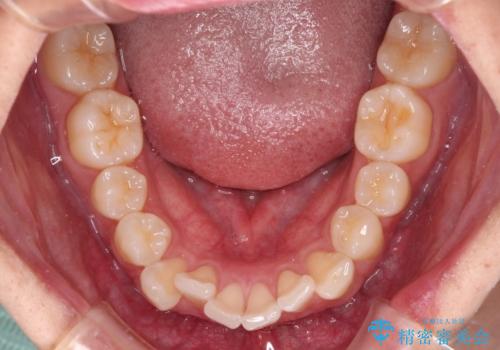

前歯のデコボコをインビザラインで綺麗に改善

- 上下前歯のデコボコとクロスバイトを気にして来院された患者様です。

インビザラインを用い、IPR(歯と歯の間を削る)と歯列全体を拡大させることで、歯並びを整えていくこととしました。

毎日22時間の装着時間を徹底してくださったのですが、左右ともに臼歯が咬合しなくなるという、インビザライン独特の症状が強く長く続いてしまい、終了するまでに長期間を要してしまいました。